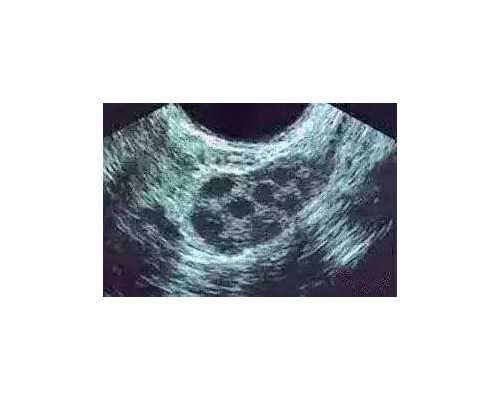

试管婴儿属于辅助生殖手段,可以进一步的解决了不孕不育难题。在正式进入试管促排周期的夫妇,在经历过十几天的促排卵后,体内的卵泡已经发育成熟了,也就是我们常说的优势卵泡。即将面临的下一步就是取卵。但是很多时候,有的患者对于取卵手术是很担忧和害怕的,因为我们经常是可以听到取卵手术会比较痛等相关信息,那么取卵手术过程是怎么样的?需要多久?痛不痛呢?北京哪些医院能够提供第三代试管技术服务?,北京市第一人民医院生殖医学中心能够提供哪些服务??